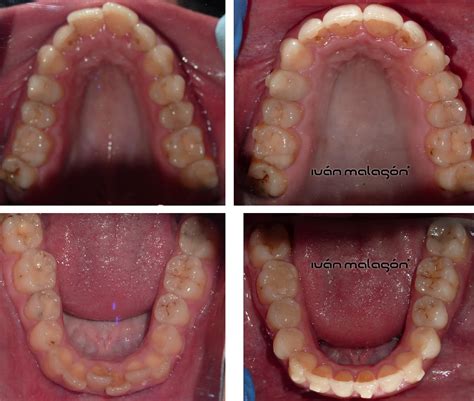

Si te fijas en un esquema anatómico de la boca, verás que los dientes se disponen en dos «arcos»: el superior y el inferior, cada uno con características particulares.

- Arcada dental superior: Se refiere a la fila de dientes que están sujetos al hueso maxilar, o la parte superior de la mandíbula. Está anclada al hueso maxilar y tiene una forma más amplia y ovalada. Esta arcada tiende a tener una forma más amplia y ovalada en comparación con la inferior. Al ser más grande, es la encargada de cubrir ligeramente la arcada inferior al morder, asegurando una oclusión adecuada. Esta disposición permite que cubra ligeramente a la arcada inferior al morder, facilitando una oclusión adecuada.

- Arcada dental inferior: En este caso, los dientes están alojados en la mandíbula inferior, un hueso móvil que participa activamente en la masticación y el habla. Situada en la mandíbula, que es la parte móvil del sistema, la arcada inferior tiene una forma más curva y estrecha. La arcada dental inferior suele tener una forma más estrecha y curva que la superior. Al ser móvil, es la que interactúa con la arcada superior durante la masticación, facilitando que los dientes trabajen en conjunto para triturar los alimentos.